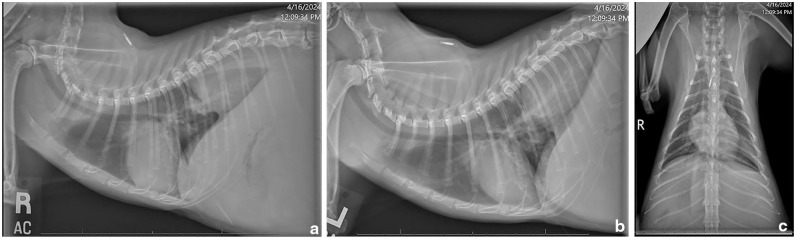

Case summary: A 4-year-old spayed female domestic shorthair cat was presented for evaluation of multiple abdominal masses and hyperglobulinemia. Thoracic radiographs and abdominal ultrasonography revealed a cranial abdominal mass with extension through the aortic hiatus of the diaphragm and into the caudodorsal mediastinum. A diagnosis of feline eosinophilic sclerosing fibroplasia (FESF) with intralesional methicillin-resistant Staphylococcus aureus (MRSA) was obtained based on necropsy results.